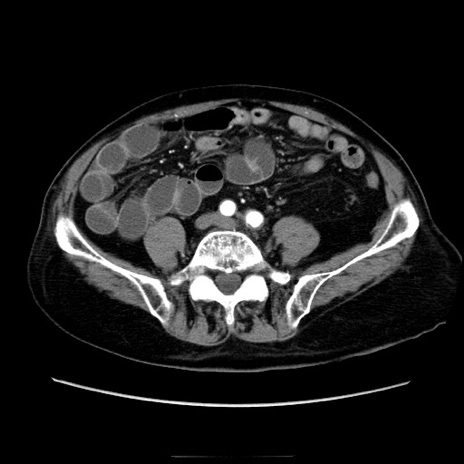

症例21(横断像)

【症例】70歳代男性

【主訴】腹痛

【現病歴】肝硬変・肝細胞癌にてかかりつけの方。約9時間前に食後より腹痛出現。症状が徐々に増悪し、嘔吐出現したため来院。

【既往歴】肝硬変、肝細胞癌(RFA、TACE後)

【身体所見】意識清明、表情苦悶様、BT 36℃、BP 129/78mmHg、P 88bpm、SpO2 97%(RA)、右上腹部から心窩部にかけて圧痛あり、反跳痛なし、筋性防御あり。

【データ】WBC 5800、CRP 0.16